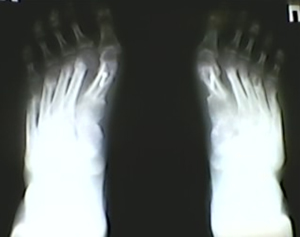

«Продольно-поперечное плоскостопие, вальгусное отклонение первых пальцев, молот-кообразные деформации 2, 3, 4 пальцев, метатарзалгия обеих стоп» (рис. 2, 3). Были произведены следующие реконструктивные операции на передних отделах стоп: остеотомии SCARF первых плюсневых костей, остеотомии Weil 2, 3, 4, 5 плюсневых костей. Уже в раннем послеоперационном периоде был отмечен неудовлетворительный результат: вальгусное отклонение первых пальцев сохранялось, также имело место вальгусное отклонение 2, 3, 4 плюсневых костей. Через 3 месяца появилась боль под головками 3, 4 плюсневых костей. В течение года боли под головками 3,4 продолжали нарастать.

Пациентка была повторно госпитализирована. После выполнения ревизионной операции (Артродез медиальных плюснеклиновидных суставов, проксимальная остеотомия 2,3, 4 плюсневых костей) клинически и рентгенологически коррекция была достигнута. Через 3 месяца после операции пациентка была довольна результатом, косметический дефект устранен, боли отсутствуют (рис. 4, 5).